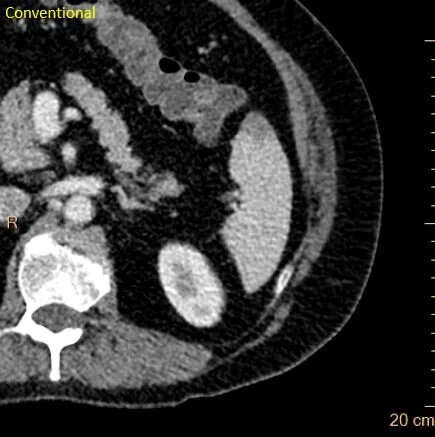

Hypodensity right kidney lower pole. Could be pyelonephritis or infarct.

Here is another hypodensity. UA was clean. So these are most likely infarcts.